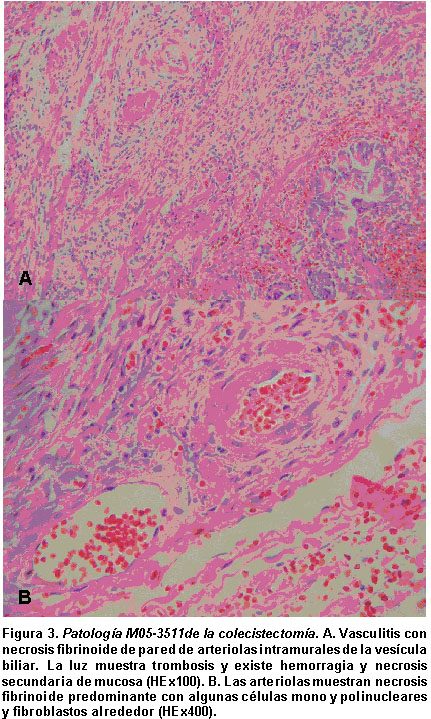

La niña se lleva a cirugía y se le practica colecistectomía laparoscópica que evidencia macroscópicamente vesícula aumentada de tamaño, con cambios inflamatorios y líquido claro intraperitoneal. Histopatológicamente se encuentran las paredes de la vesícula engrosadas con fibrosis e infiltrado inflamatorio agudo que compromete todo su espesor y cambios vasculíticos agudos de las arterias (Figura 3). La evolución postquirúrgica fue satisfactoria.

En el presente caso, la paciente inició el dolor abdominal con reactivación de la enfermedad como se mostró con los laboratorios: anemia severa con coombs positivo, consumo de C3 y C4, marcado compromiso renal con proteinuria nefrótica, hipoalbuminemia, hipercolesterolemia y aumento de creatinina sérica a 1.6 mg/dl (Cuadro 1). La terapia inmunosupresora que se le dio con pulsos de metilprednisolona y ciclofosfamida endovenosa, no lograron controlar la vasculitis que se evidenció en la patología (Figura 3).